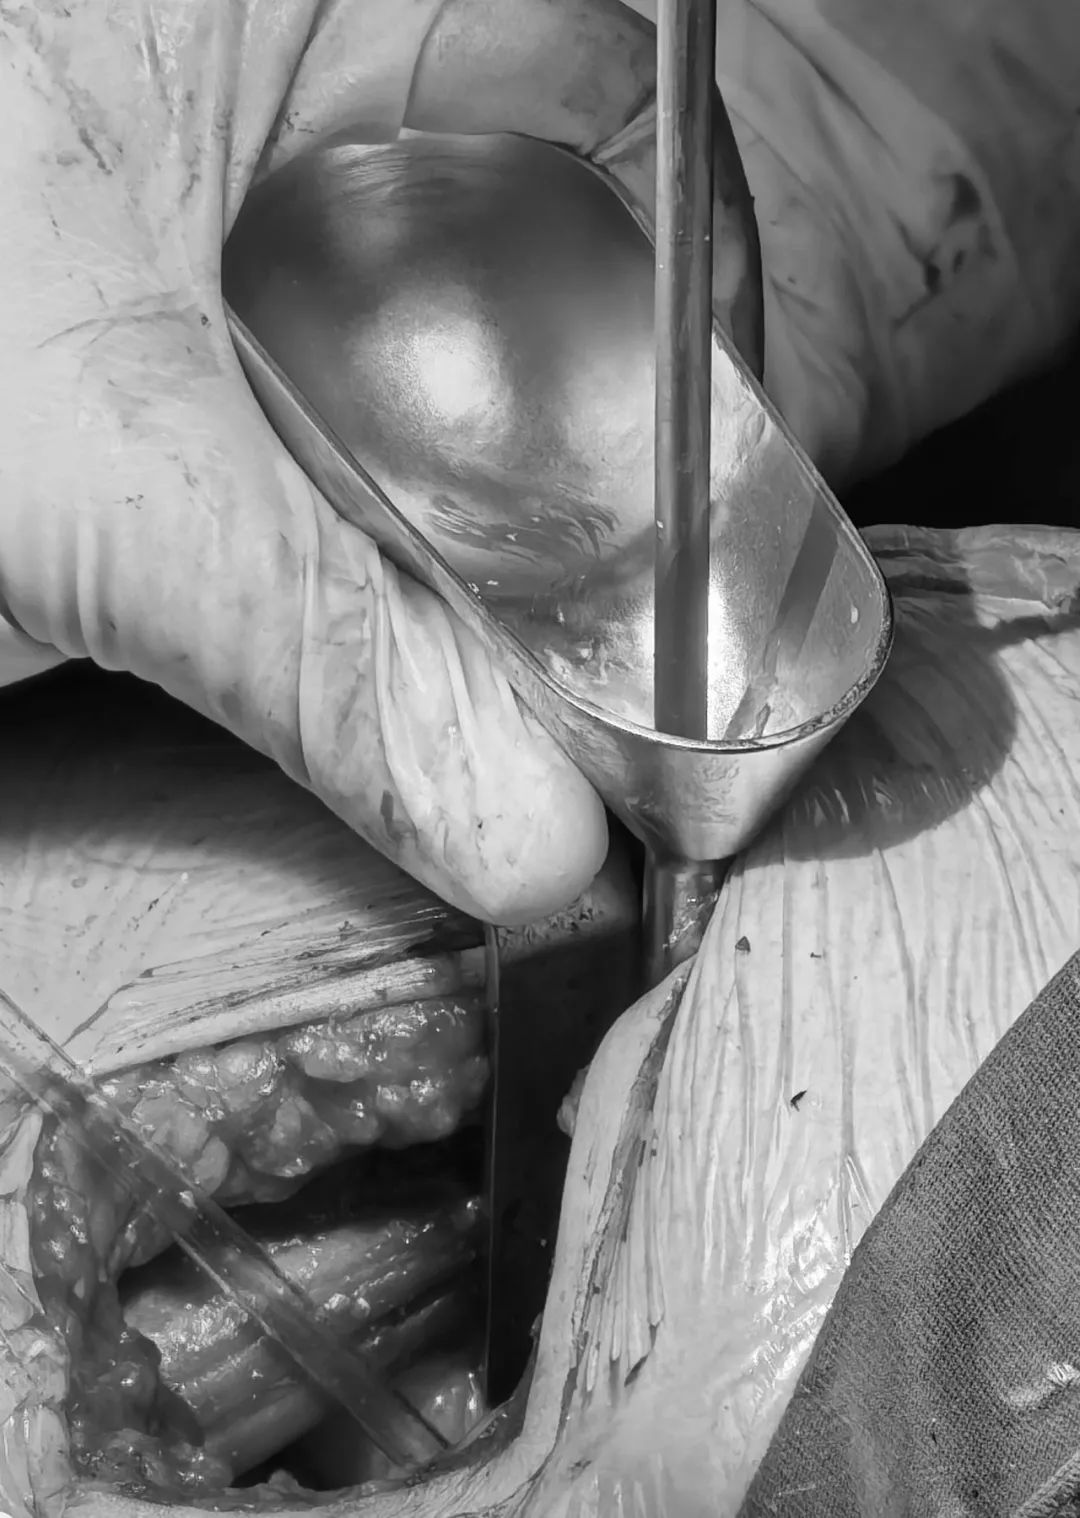

取出前次不融合的cage,并處理椎間隙

L4/L5依次試用試模,確認(rèn)Uni-L自穩(wěn)定型腰椎融合器選用大小

Uni-L自穩(wěn)定型腰椎融合器內(nèi)植骨

L4/L5植入Uni-L自穩(wěn)定型腰椎融合器